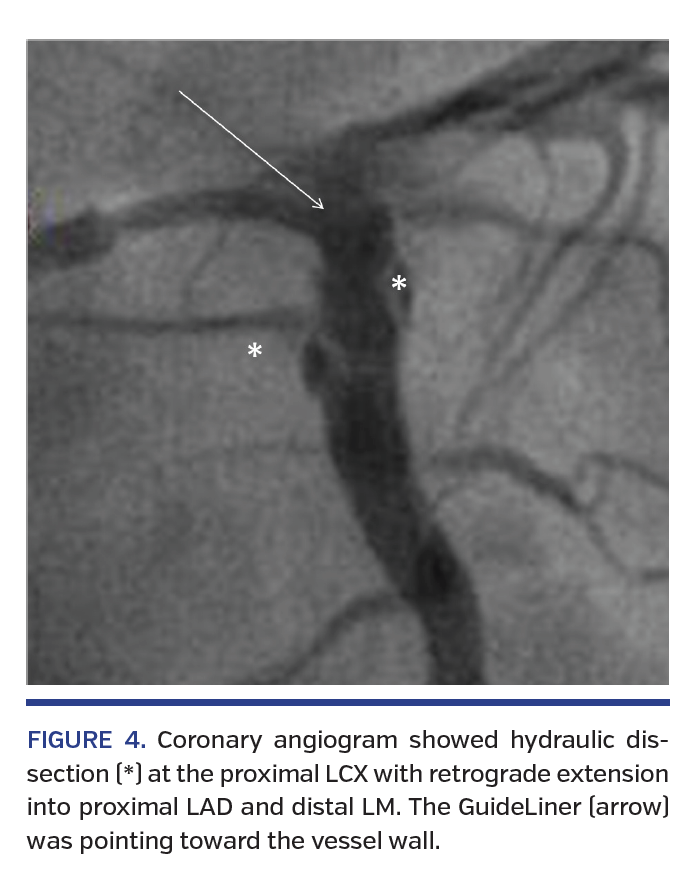

Angiography after OCT acquisition showed hydraulic spiral dissection from the proximal LCX extending retrograde into the proximal LAD and distal left main (LM) stem (Figures 3 and 4; Video 2). A 4.0 mm semicompliant (SC) balloon was immediately inflated at the LCX dissection site for 1 minute. Subsequent angiogram with balloon occlusion of the LCX showed patent LAD with no contrast staining (Figure 5). A 4 x 24 mm DES was implanted from the LM into the LCX, overlapping the initial LCX stent. The final angiogram was satisfactory and the patient remained stable throughout the procedure.

Mother-and-child catheter pairing the GuideLiner support catheter delivered through a standard guiding catheter permits deep intubation of the target vessel to provide coaxial back-up support to facilitate stent delivery across heavily calcified lesions in tortuous vessels and selective contrast injection. In this case, the soft tip of the GuideLiner was not coaxial to the tortuous LCX and likely abutted the vessel wall or plaque despite no warning of pressure damping before contrast injection during OCT acquisition. Focal hydraulic pressure generated by short and forceful hand contrast injection could easily create a crack at a vulnerable plaque and track into the injury point, resulting in coronary dissection. Therefore, positioning of the GuideLiner for OCT acquisition in tortuous vessels requires special attention to avoid iatrogenic dissection.